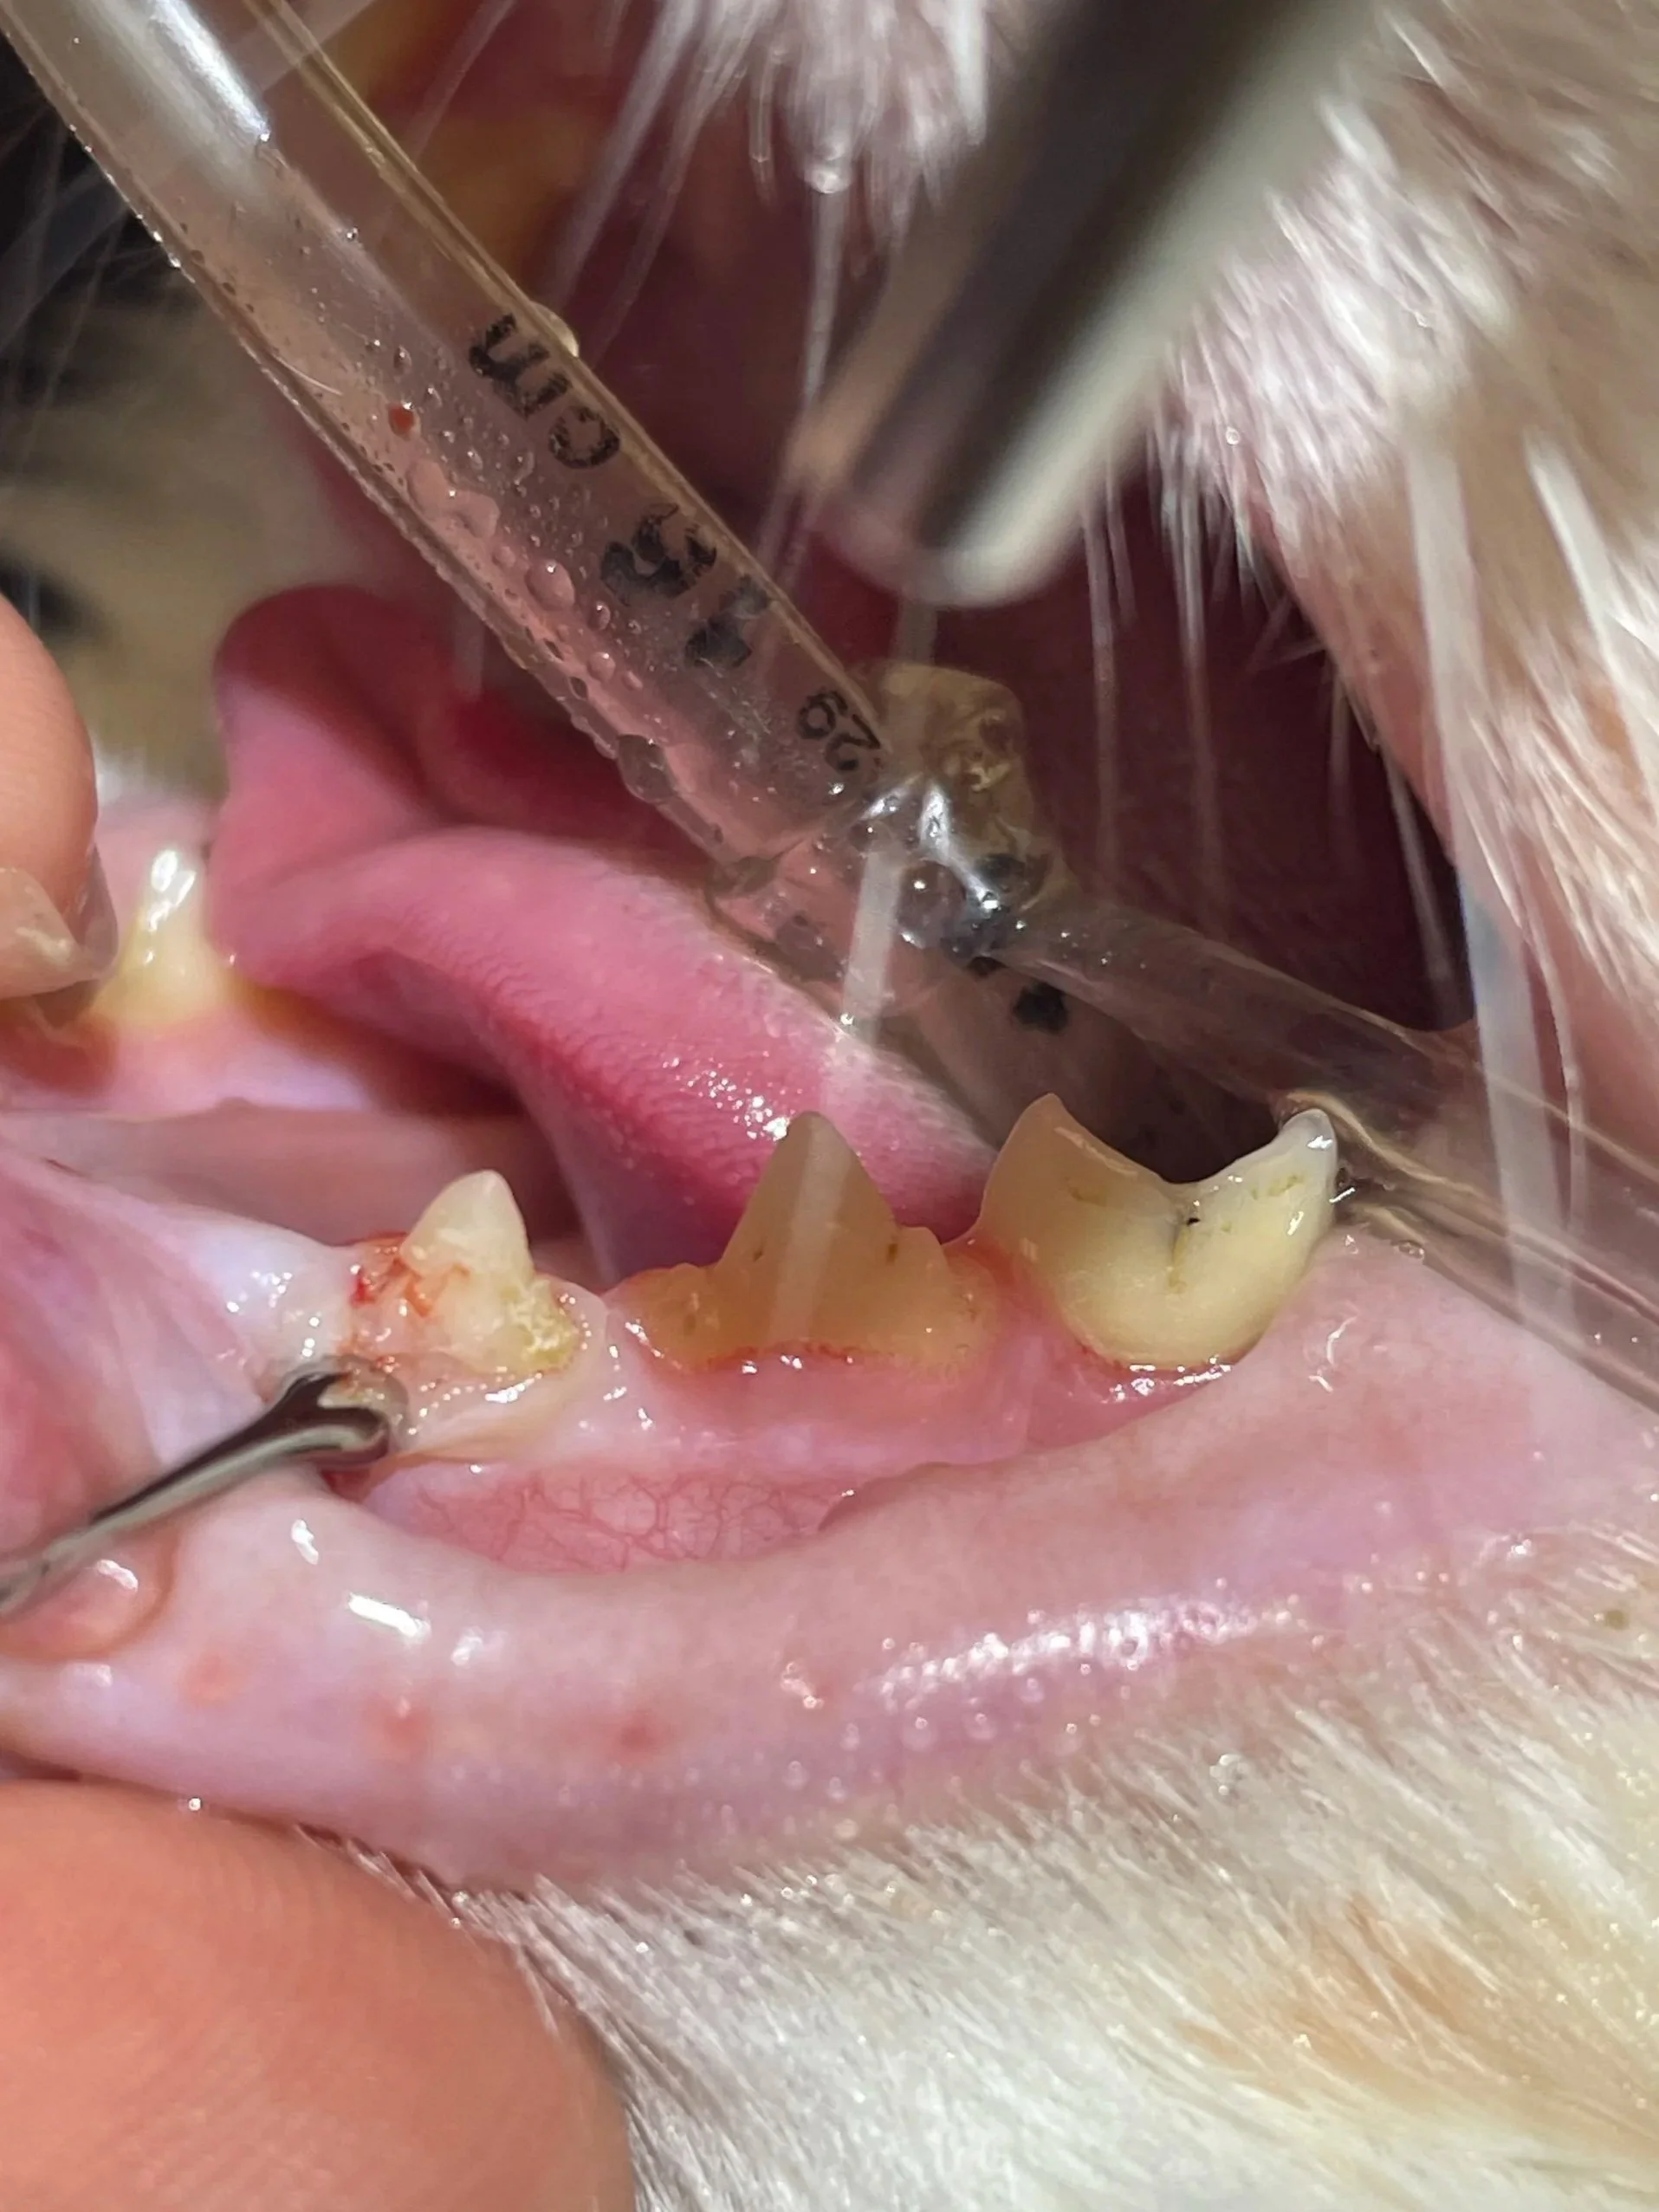

• After dental imaging has been completed, we perform a thorough oral examination. This is the only appropriate way to fully assess the mouth—by pairing dental X-rays with hands-on evaluation.

Using specialized dental instruments, we carefully assess:

• Pocketing: measuring the depth around each tooth to check for periodontal disease

• Mobility: determining if a tooth has become loose from bone loss

• Furcation exposure: evaluating the area where roots divide in multi-rooted teeth

• Gingival and tooth health: identifying inflammation, fractures, or other pathology

When combined with X-rays, this oral exam provides a complete picture of your pet’s dental health and allows us to make the best recommendations for treatment.